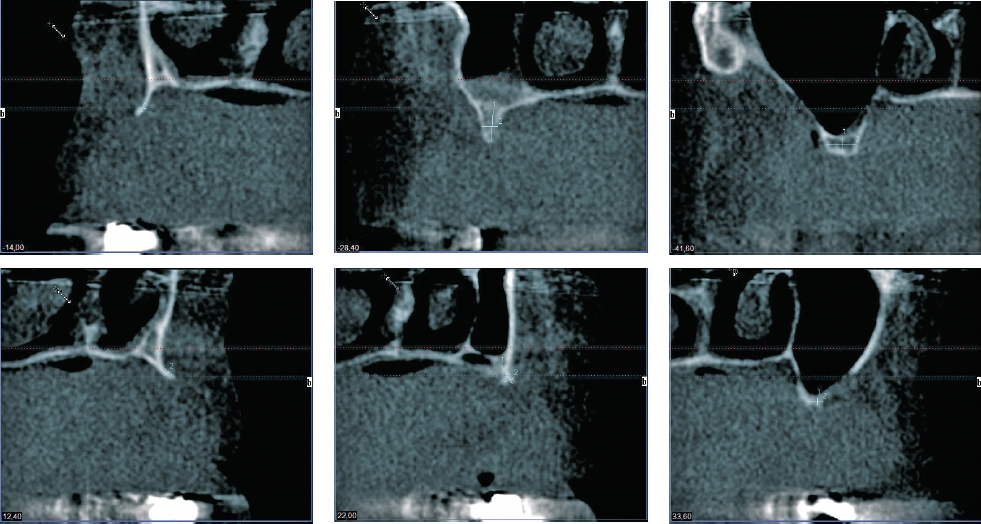

Die Transplantate werden, basierend auf einem dreidimensionalen Bild (CT/DVT), in der CAD-Software konstruiert und mittels CAM-Frästechnologie nach hohen Qualitätsstandards hergestellt. Die so gefertigten Knochenblöcke werden vom Autor seit mehr als zehn Jahren verwendet. Der maxgraft bonebuilder (Botiss, Berlin) ermöglicht u. a. komplexe horizontale und vertikale Augmentationen, ohne den Patienten durch Entnahme von Eigenknochen zu belasten. Zudem kann eine maximale Kontaktfläche mit dem ortsständigen Knochen erreicht werden. Da eine manuelle Anpassung während des chirurgischen Eingriffs wegfällt, verkürzt sich die Operationszeit deutlich. Diese signifikant reduzierte Operationszeit, die Schmerzreduktion und die zu erwartende verbesserte Wundheilung sprachen auch im vorliegenden Fall für diese Option.

Aufgrund der hochgradigen Atrophie des Kieferknochens war für die geplante implantatprothetische Versorgung eine absolute Kieferkammerhöhung notwendig. Nach gründlicher Anamnese und Patientenaufklärung begann die Behandlung.

Erweitertes Backward Planning